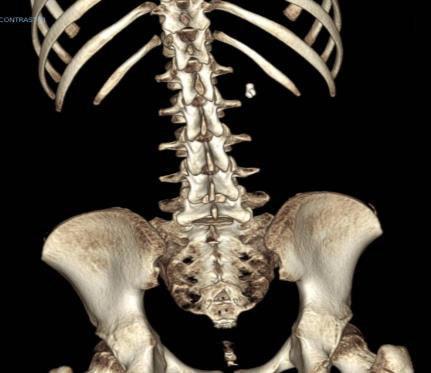

Adductor Longus L2, L3

Vastus Lateralis L3,L4

Tibialis Anterior L4, L5

Peroneus longus L5, S1

Gastrocnemius S1, S2

Abductor hallucis S1, S2

Sphincter S2